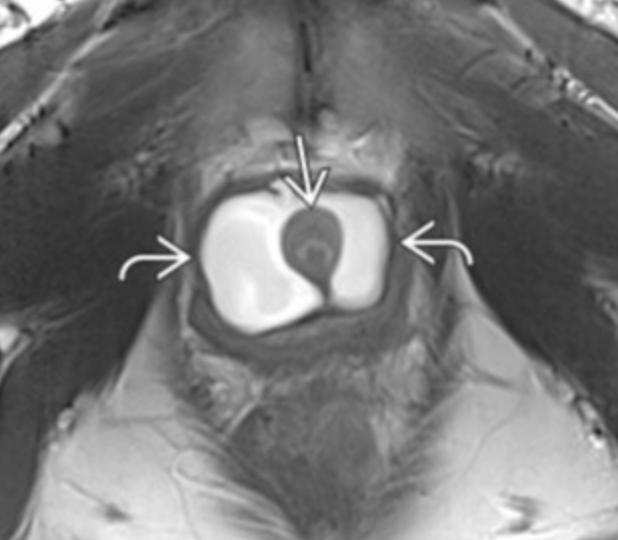

• Cystic fluid collection surrounding the urethra

• Presents as triad of 3Ds

• Dysuria

• Dyspareunia

• Postvoid Dribbling